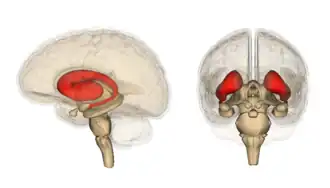

Het corpus striatum[1] is een gebied in de grote hersenen dat onder de schors van de grote hersenen (cortex cerebri) ligt. Het corpus striatum vormt een belangrijk onderdeel van de basale kernen en is daarmee onderdeel van de regelkring voor het versterken, afremmen en bijsturen van de motorische activiteit die uitgaat van de cortex cerebri.

Het corpus striatum is op te delen in het striatum dorsale, bestaande uit de nucleus caudatus en het putamen, en het striatum ventrale, bestaande uit de nucleus accumbens en delen van het tuberculum olfactorium. Bepaalde delen van de nucleus caudatus en het putamen worden ook tot het striatum ventrale gerekend.